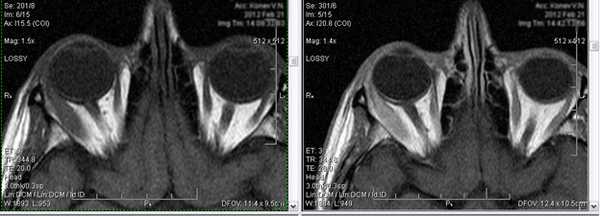

Тот же пациент, исследование в динамике через 4,5 года

Исследование в 2008 году Исследование в 2013 году